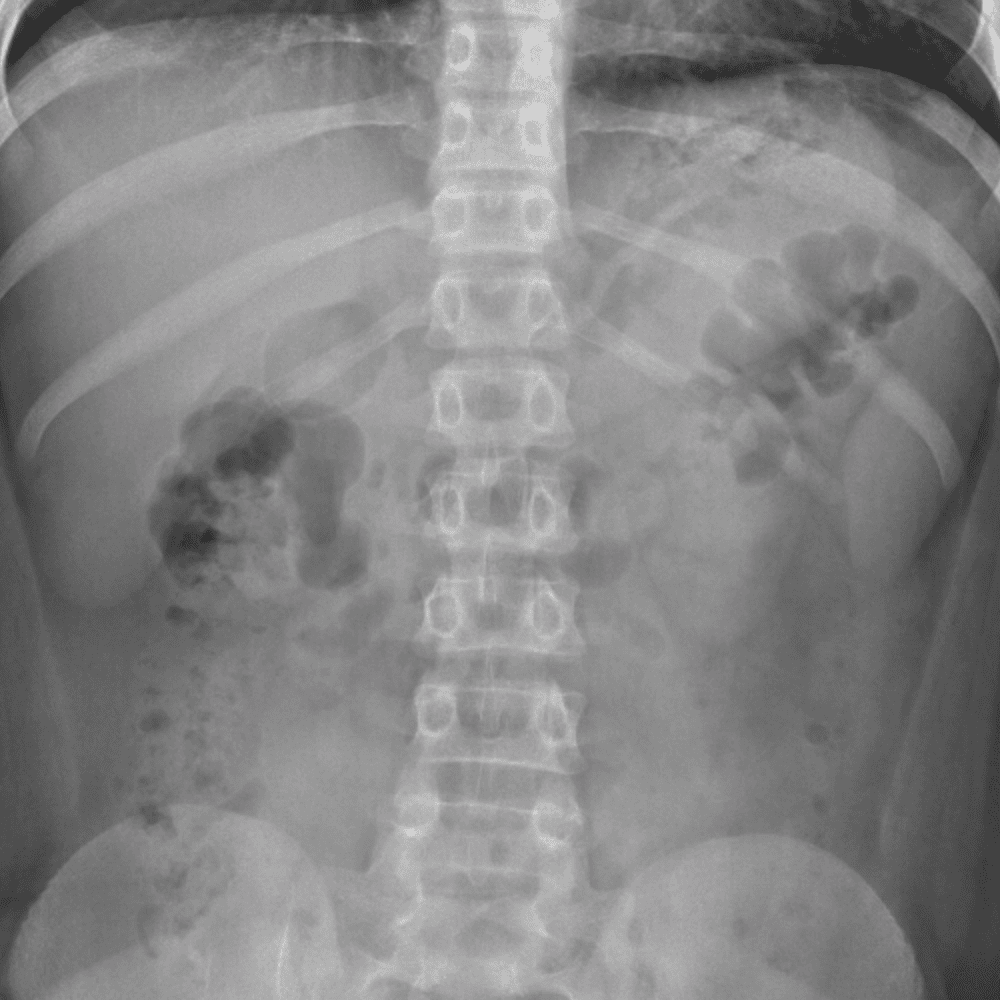

Peds Abdomen

Practice

Simulates call by including subtle or difficult cases and some normals.

30 cases